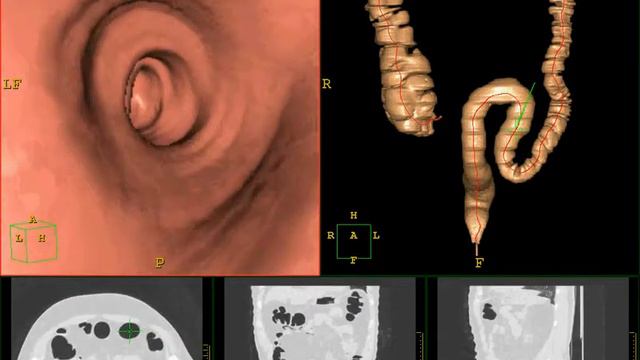

В "Медицинском городе" используются самые современные технологии диагностики. Одна из них - виртуальная колоноскопия. Её особенность в том, что исследование проводится без прямого контакта с кишечником пациента.